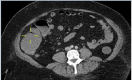

Unusual cause of colonic mucosal ulceration and gastrointestinal bleeding

Keywords: colorectal pathology; gastrointestinal bleeding.